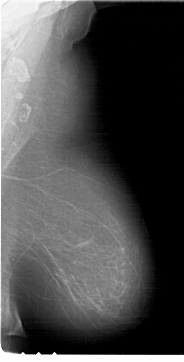

A_1617_1.LEFT_MLO

LEFT_MLO LINES 6091 PIXELS_PER_LINE 4531 BITS_PER_PIXEL 12 RESOLUTION 43.5 OVERLAY